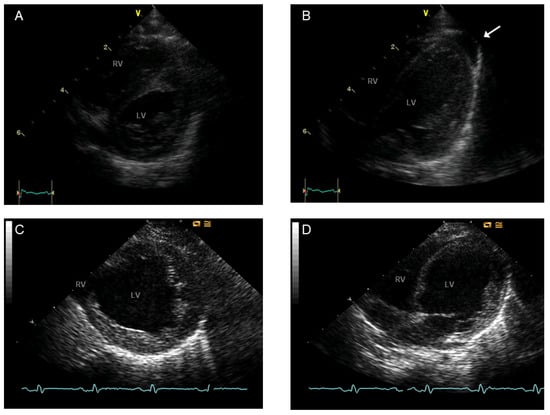

- Villalba-Orero, M.; Lopez-Olaneta, M.M.; Gonzalez-Lopez, E.; Padron-Barthe, L.; Gomez-Salinero, J.M.; Garcia-Prieto, J.; Wai, T.; Garcia-Pavia, P.; Ibanez, B.; Jimenez-Borreguero, L.J.; et al. Lung ultrasound as a translational approach for non-invasive assessment of heart failure with reduced or preserved ejection fraction in mice. Cardiovasc. Res. 2017, 113, 1113–1123. [Google Scholar] [CrossRef]